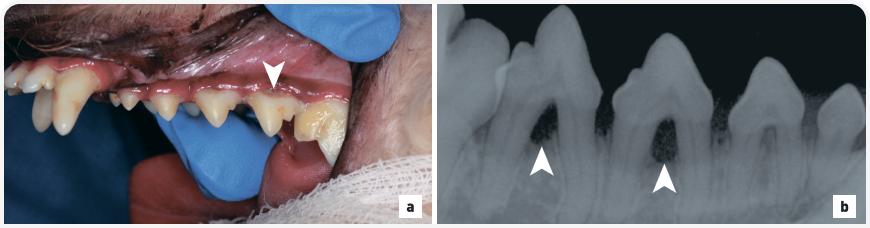

Рисунок 1. (a) Тяжелая степень отложения зубного камня на левых премолярах верхней челюсти у чихуахуа. Обратите внимание, что пациент располагается в дорсальном лежачем положении для осмотра ротовой полости под общей анестезией. (b) Внутриротовая рентгенограмма зубов (левая латеральная проекция клыка, техника деления угла пополам) показывает верхние левые третий резец, клык и премоляры с первого по третий. Наблюдается легкий пародонтит, показания к удалению отсутствуют. Обратите внимание на значительное отложение зубного камня на коронке левого третьего премоляра верхней челюсти (стрелка).

Количество сформировавшегося зубного налета, а также зубного камня не всегда коррелирует со степенью тяжести пародонтита. У некоторых собак мелких пород при осмотре полости рта выявляется значительное отложение зубного камня, но при этом по результатам рентгенографии диагностируется легкая форма пародонтита (Рис. 1). У других собак стадия заболевания оказывается гораздо серьезнее, чем можно было бы предположить по количеству зубного камня (Рис. 2). Оценка степени тяжести пародонтита при осмотре полости рта у собаки является важным компонентом общего физикального осмотра. Однако чтобы определить истинный масштаб поражения и, соответственно, назначить необходимое лечение заболевания, необходимо тщательное обследование пациента под общей анестезией, включая измерение глубины зубодесневых карманов, рентгенографию зубов.

Рисунок 2. (a) Легкое отложение налета и зубного камня на правых премолярах нижней челюсти у той-пуделя в возрасте 2 лет. Обратите внимание, что пациент располагается в дорсальном лежачем положении для осмотра ротовой полости под общей анестезией. В области фуркации правого четвертого премоляра нижней челюсти видна легкая рецессия десны с накоплением зубного налета (стрелка). Владелец чистил зубы этой собаке два раза в день. (b) Внутриротовая рентгенография зубов (визуализация правых премоляров, техника деления угла пополам) демонстрирует тяжелый пародонтит, характеризующийся обнажением фуркации третьего и четвертого премоляров (стрелки). Данные зубы были удалены без осложнений, наряду с несколькими другими зубами вследствие тяжелого пародонтита.